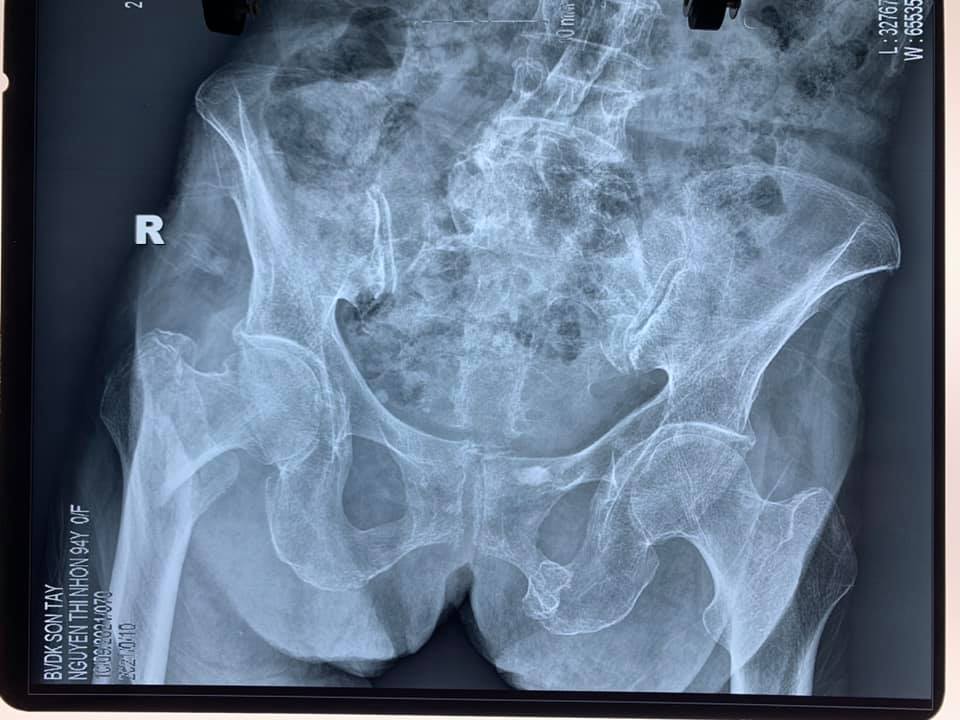

Trước đó, ngày 14/9/2021 bệnh viện cũng đã phẫu thuật thay khớp háng bán phần không xi măng cho bệnh nhân Nguyễn Thị N 94 tuổi ở tại Lê Lợi – Sơn Tây – Hà Nội.